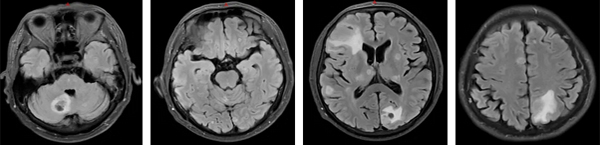

治疗前(2020年6月)

治疗5年(2025年6月)